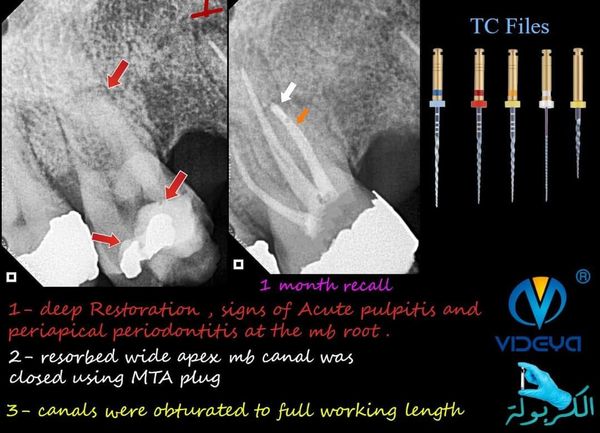

it was just a routine endodontic treatment for first upper molar with acute pulpitis till my apex locator (bomedent) which i trust went mad in the mesiobuccal canal.

all canals length were on average but MB canal was about 16 mm which is very abnormal and goes against my preoperative radiograph.

on A CBCT view the mb canal had a periapical lesion that caused a pathologically resorbed wide open apex with leakage of large amount of fluid into the canal.

the canal was retreated till the full working length and after 3 visits we managed to get a dry canal, apical 3rd was closed using MTA & MTA Carier .6 (angelus).

then obturation material was set to the remaining canal space, case reported a post operative moderate pain that lasted for 24 hour, after 1 month follow up the case was a symptomatic and pain free.